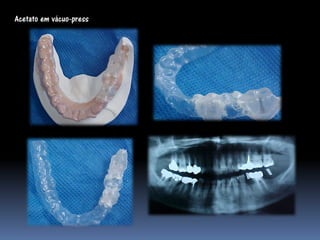

•Vácuo- press ou própria prótese do paciente

duplicada com acrílico transparente

Guia radiológico

Acetato em vácuo-press

Acrílico com tubos

Acetato com lâmina metálica